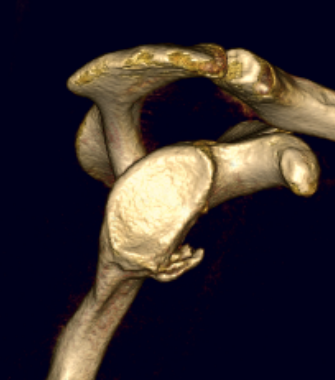

Bony bankart 3D CT with humeral head subtraction

Hill Sachs

Hill Sachs 3D CT